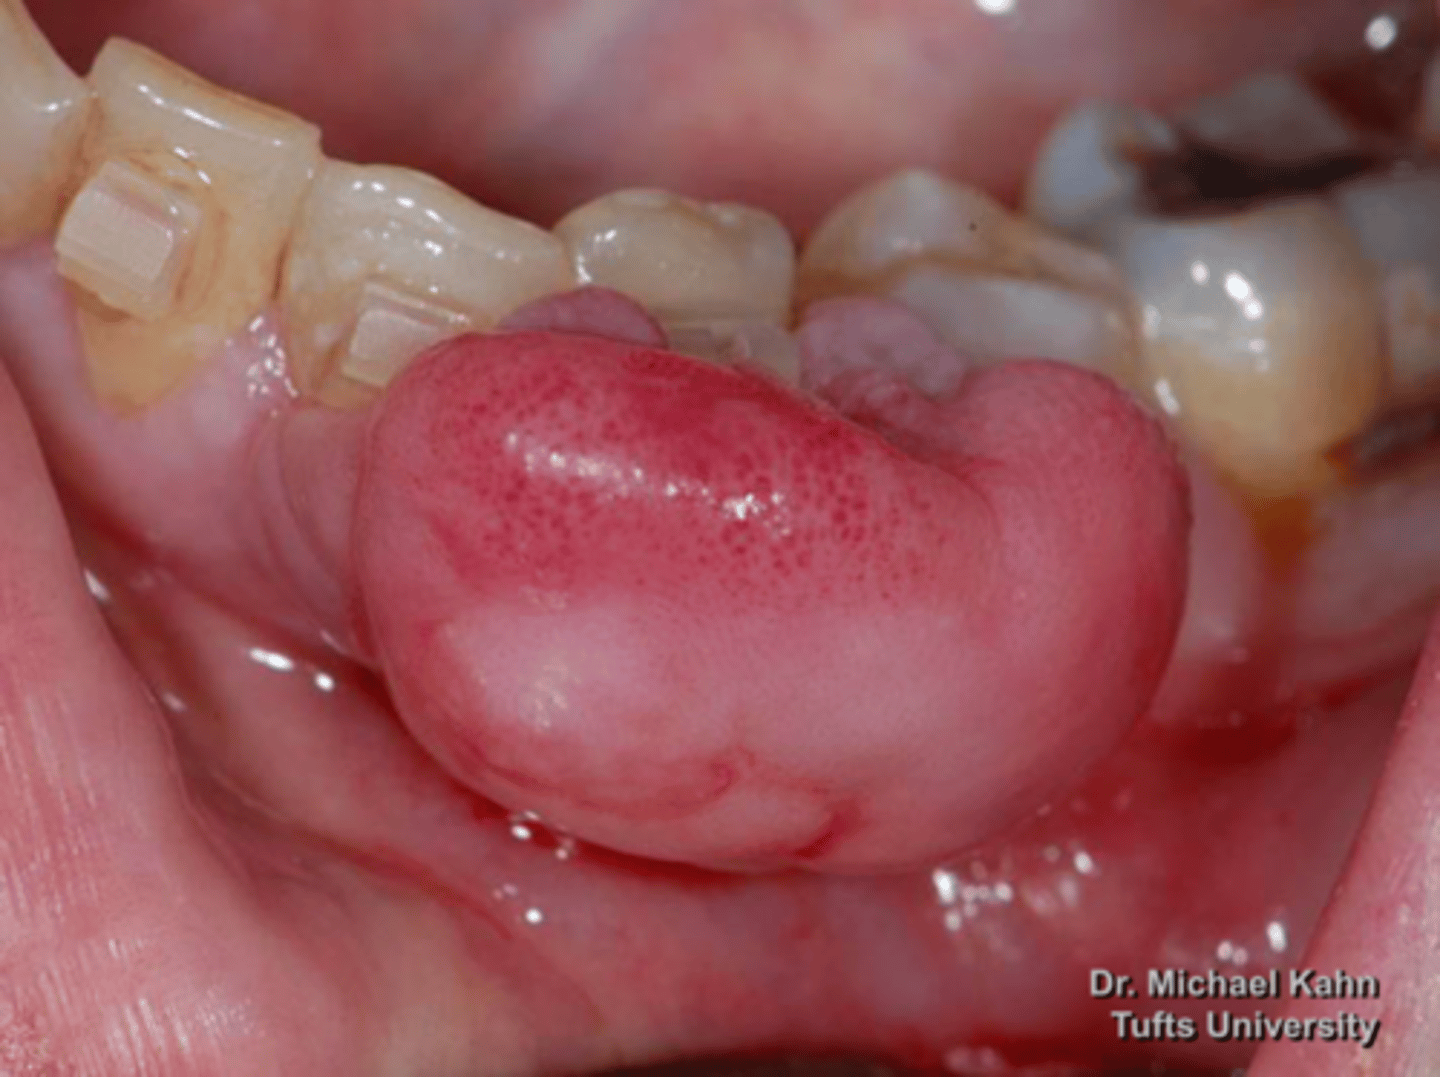

Pyogenic Granuloma

male patient presents with red-pink ulcerated nodule on the facial aspect of the maxillary gingiva. Histopathology shows vascular proliferation of granulation tissue. What do you suspect?

Pyogenic Granuloma

Vascular proliferation of granulation tissue is associated with what pathology?

gingiva

75% of Pyogenic Granulomas present of what location?

conservative excision

eliminate irritants

what is the treatment for Pyogenic Granulomas?